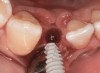

Fig 38. A reverse-torque screw was placed into the implant.

Figure 38

Fig 39. A counter-torque device was placed over the reverse-torque screw.

Figure 39

Fig 40. The implant was easily unscrewed within minutes in a minimally invasive manner with less trauma to the surgical site.

Figure 40

The crown and screw-retained custom abutment were removed, and a surgical cover screw was placed into the implant, thereby allowing spontaneous gingival augmentation in situ (Figure 33 and Figure 34). Note that the lingual aspect of the implant site was significantly more coronal than the labial aspect, which was positive because the defect would be limited to a facial–lingual defect. A fixed RBR bridge was cemented on the adjacent teeth and used as a tooth-supported transitional provisional restoration (Figure 35). A few weeks were allotted to let the soft tissue heal and migrate around the cover screw (Figure 36) to see if there would be complete coverage, thereby allowing a soft-tissue augmentation procedure to be performed with primary flap closure as in clinical scenario No. 2. The major obstacle in achieving a positive tissue response was that the implant depth was also deficient because the implant–abutment connection was at the level of the free gingival margin. It was decided that the best treatment option would be to remove the implant. A high-powered reverse-torque device (Fixture Remover Kit, NeoBiotech, www.neobiotechus.com) was used to remove the implant atraumatically (Figure 38 through Figure 41). The implant socket was allowed to heal for several months not unlike an extracted tooth (Figure 42). A new implant was placed in a better position from both a restorative and esthetic perspective (Figure 43), and after a few months of healing, a new crown was made (Figure 44). A satisfactory functional and esthetic result was achieved (Figure 45 and Figure 46) without employing pink porcelain.